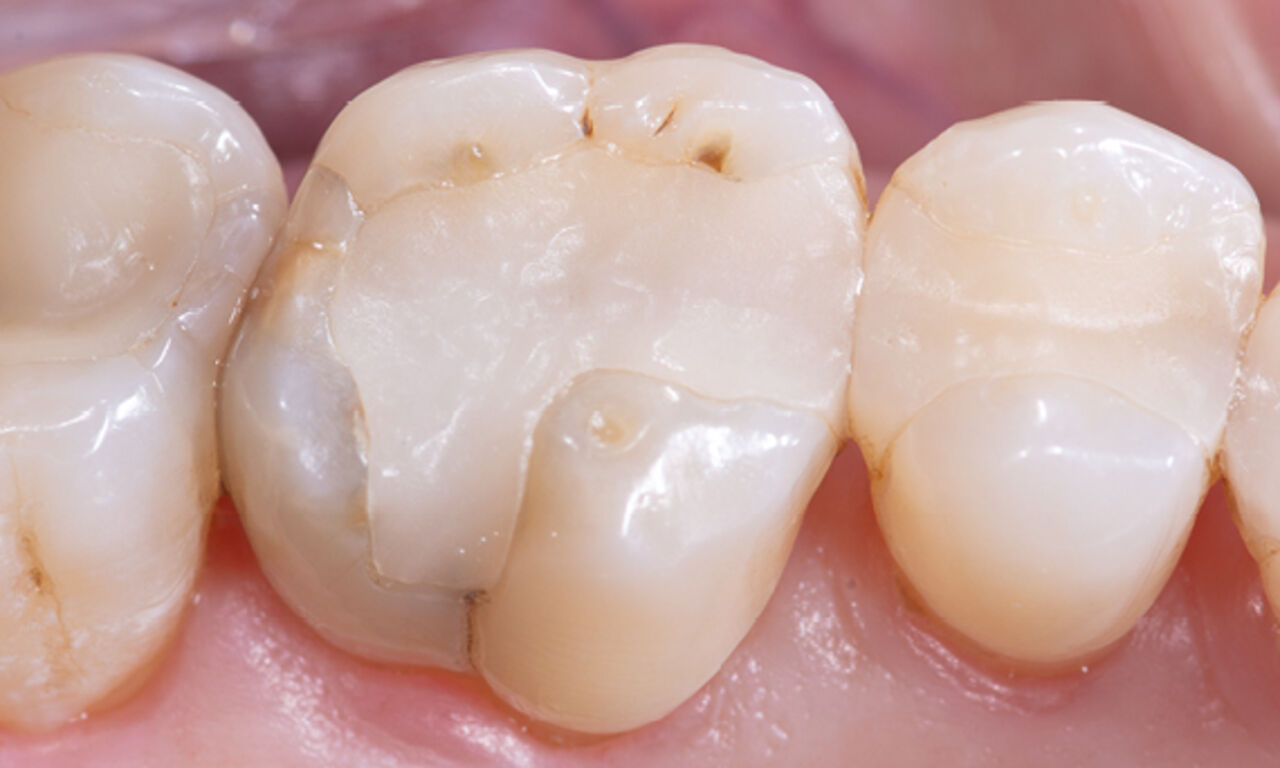

Composite filling, tooth 16, before CEREC treatment

Before

Large insufficiency of the composite filling on tooth 16 with distal marginal ridge cracks, a lingual wall crack and distal recurrent decay.